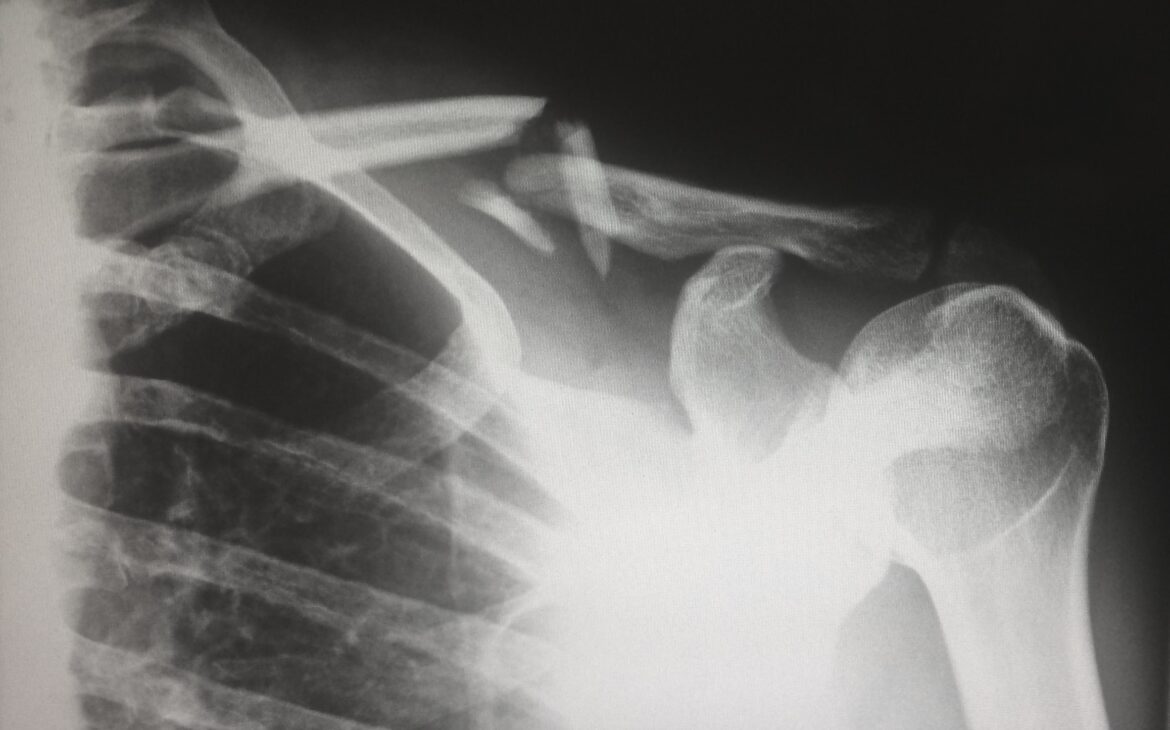

Si has tenido fracturas, es probable que tengas una deficiencia de Vitamina D

La deficiencia de Vitamina D es más común de lo que podrías pensar. De acuerdo a los expertos, es una epidemia en todo el mundo. Se calcula que la mitad de los jóvenes podrían padecerla y casi 90% de los adultos mayores, sobre todo los que tienen antecedes de fracturas. En este artículo descubrirás el rol de la vitamina D en el cuerpo, factores de riesgo de deficiencia de Vitamina D, cómo diagnosticar una deficiencia y cómo tratarla.

Su rol principal es el de regular los niveles de calcio y potasio en el cuerpo. A su vez, estos minerales ayudan a mantener los huesos, dientes y músculos en un estado óptimo de salud. Por lo tanto, una deficiencia puede causar deformidades en los huesos (por ejemplo raquitismo en niños) y problemas óseos en los adultos (como osteomalacia, reflejado en dolor de huesos constante e incluso fracturas)

La deficiencia de Vitamina D se ha relacionado con fatiga, depresión y problemas óseos. La alteración en el metabolismo del calcio incluye la disminución de absorción intestinal de calcio, lo cual causa pérdida de densidad ósea. Por lo tanto, pacientes con fracturas previas y riesgos de caídas, deben ser evaluados para reducir el riesgo de más daños a la estructura ósea. Las probabilidades de que un adulto mayor que presenta fracturas tenga una deficiencia severa de Vitamina D, son elevadas, casi del 100%.

- Fracturas de cadera: especialmente en adultos mayores